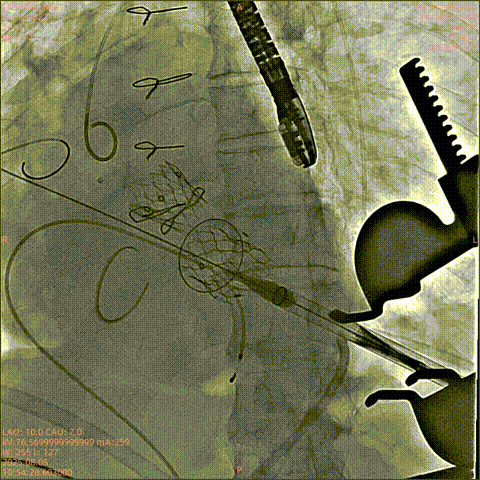

泥鳅导丝配合多功能导管跨二尖瓣,置入加硬导丝建立通路

瓣膜释放,位置良好

主动根部造影,冠脉显影良好,无漏

回收输送系统,撤出体外,无需造影,收紧荷包